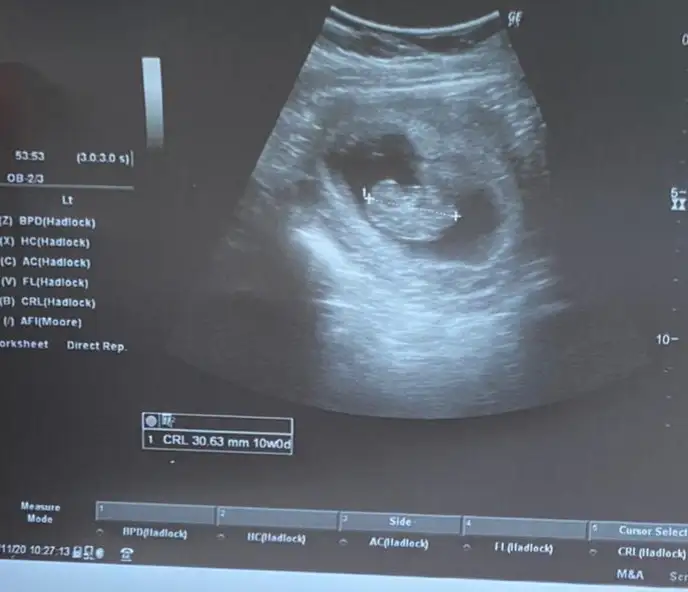

Şimdilik erkek yönünde ama en iyi 11 12 13 haftalar olmalıRica etsem bize de bakar mısınızburada 10+4

çok teşekkür ederim❤Şimdilik erkek yönünde ama en iyi 11 12 13 haftalar olmalı